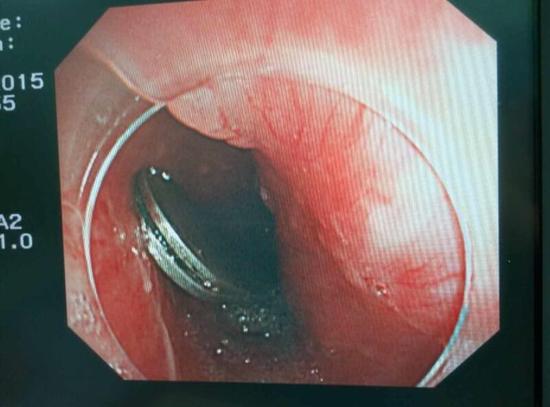

醫生從華先生胃里取出的鑷子和打火機

手術中,范醫生通過胃鏡準確發現了胃里的鑷子。但讓他驚訝的是,在華先生胃底竟然還躺著三個被腐蝕了的打火機,打火機的金屬部件都已經不見了。

隨后,范醫生先用圈套器套取出了長10厘米的鑷子,再一個一個地取出了打火機。整個取出過程小心謹慎而又一氣呵成,只用了不到10分鐘。